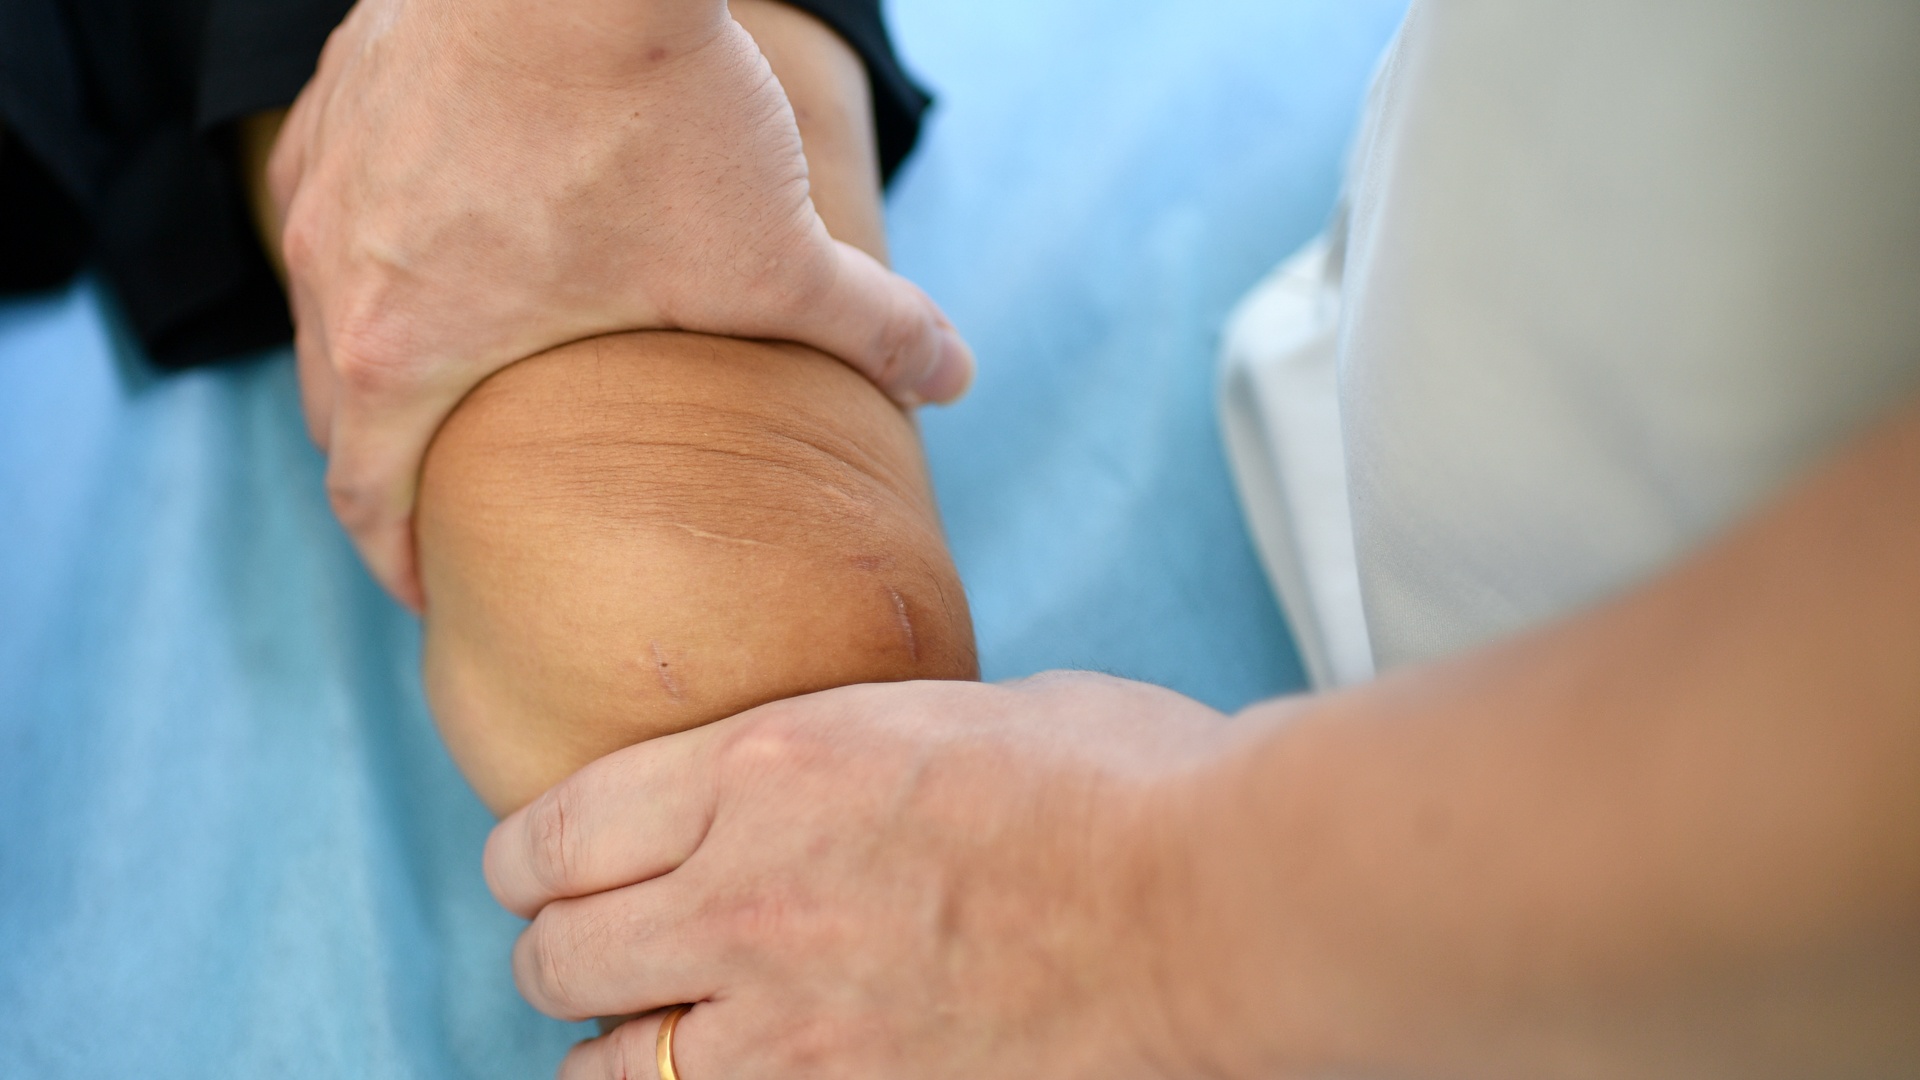

| Vợ đưa tôi đến Trung tâm Chấn thương chỉnh hình - BVĐK Tâm Anh TP.HCM để khám và chụp chiếu vì ở đây có tiếng về điều trị chấn thương thể thao, lại có máy móc chụp chiếu hiện đại. Bác sĩ Trần Anh Vũ (Trưởng khoa Y học thể thao - Phó giám đốc Trung tâm) thăm khám và kết luận chấn thương cho tôi từ ngày đầu, cũng là người trực tiếp thực hiện ca phẫu thuật. Trước ngày mổ, anh thường qua phòng bệnh trò chuyện với tôi. Sự ân cần của anh cũng như các điều dưỡng khiến tôi cảm thấy yên tâm hơn nhiều. |